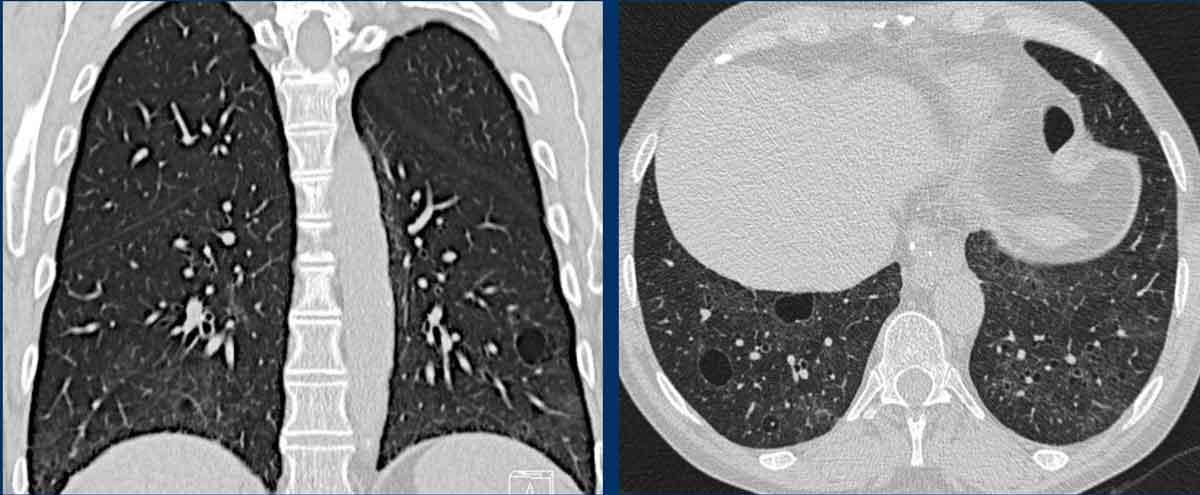

Hình ảnh

- Nhiều nang ở một phụ nữ trẻ. Lưu ý hình dạng tròn đều và phân bố lan tỏa.

- Trường hợp LAM nặng. Khi có tiền sử hút thuốc lá, chẩn đoán phân biệt cần đặt ra là LCH (giai đoạn tiến triển).

- Tràn dịch màng phổi (dịch dưỡng chấp) ở bệnh nhân LAM.

- Phân bố lan tỏa trong LAM.

Các hình ảnh này thuộc về một phụ nữ 39 tuổi với triệu chứng khó thở.

Chẩn đoán có khả năng nhất là gì?

Nhận xét hình ảnh

Có nhiều nang thành mỏng.

Lưu ý các nang phân bố đều khắp hai phổi.

Các ngách màng phổi cũng bị tổn thương (mũi tên).

Điều này cho phép loại trừ chẩn đoán LCH.

Chẩn đoán có khả năng nhất là LAM.

Đây là một ví dụ khác của LAM.

Có nhiều nang thành mỏng phân bố đều khắp hai phổi, điển hình cho LAM, nhưng trong trường hợp này kết hợp với tràn dịch màng phổi bên phải (mũi tên).

Các tế bào LAM có thể gây tắc nghẽn hệ thống bạch huyết trong lồng ngực và tạo ra tràn dịch màng phổi dưỡng chấp.

LAM là bệnh phổi dạng nang duy nhất có thể thấy sự kết hợp giữa các nang và tràn dịch màng phổi.

Ngoài ra, nhiều u cơ mỡ mạch máu (angiomyolipoma) được phát hiện ở vùng bụng trên.

Bệnh nhân này được xác định mắc LAM liên quan đến phức hợp xơ cứng củ (TSC – tuberous sclerosis complex).

Tỷ lệ hiện mắc u cơ mỡ mạch máu trong LAM tản phát là 40-50% và trong LAM liên quan TSC vào khoảng 80%.

Đây là trường hợp LAM nặng với nhu mô phổi bị tổn thương lan tỏa.

Nhìn chung, LAM là bệnh lý tiến triển với tiên lượng xấu.